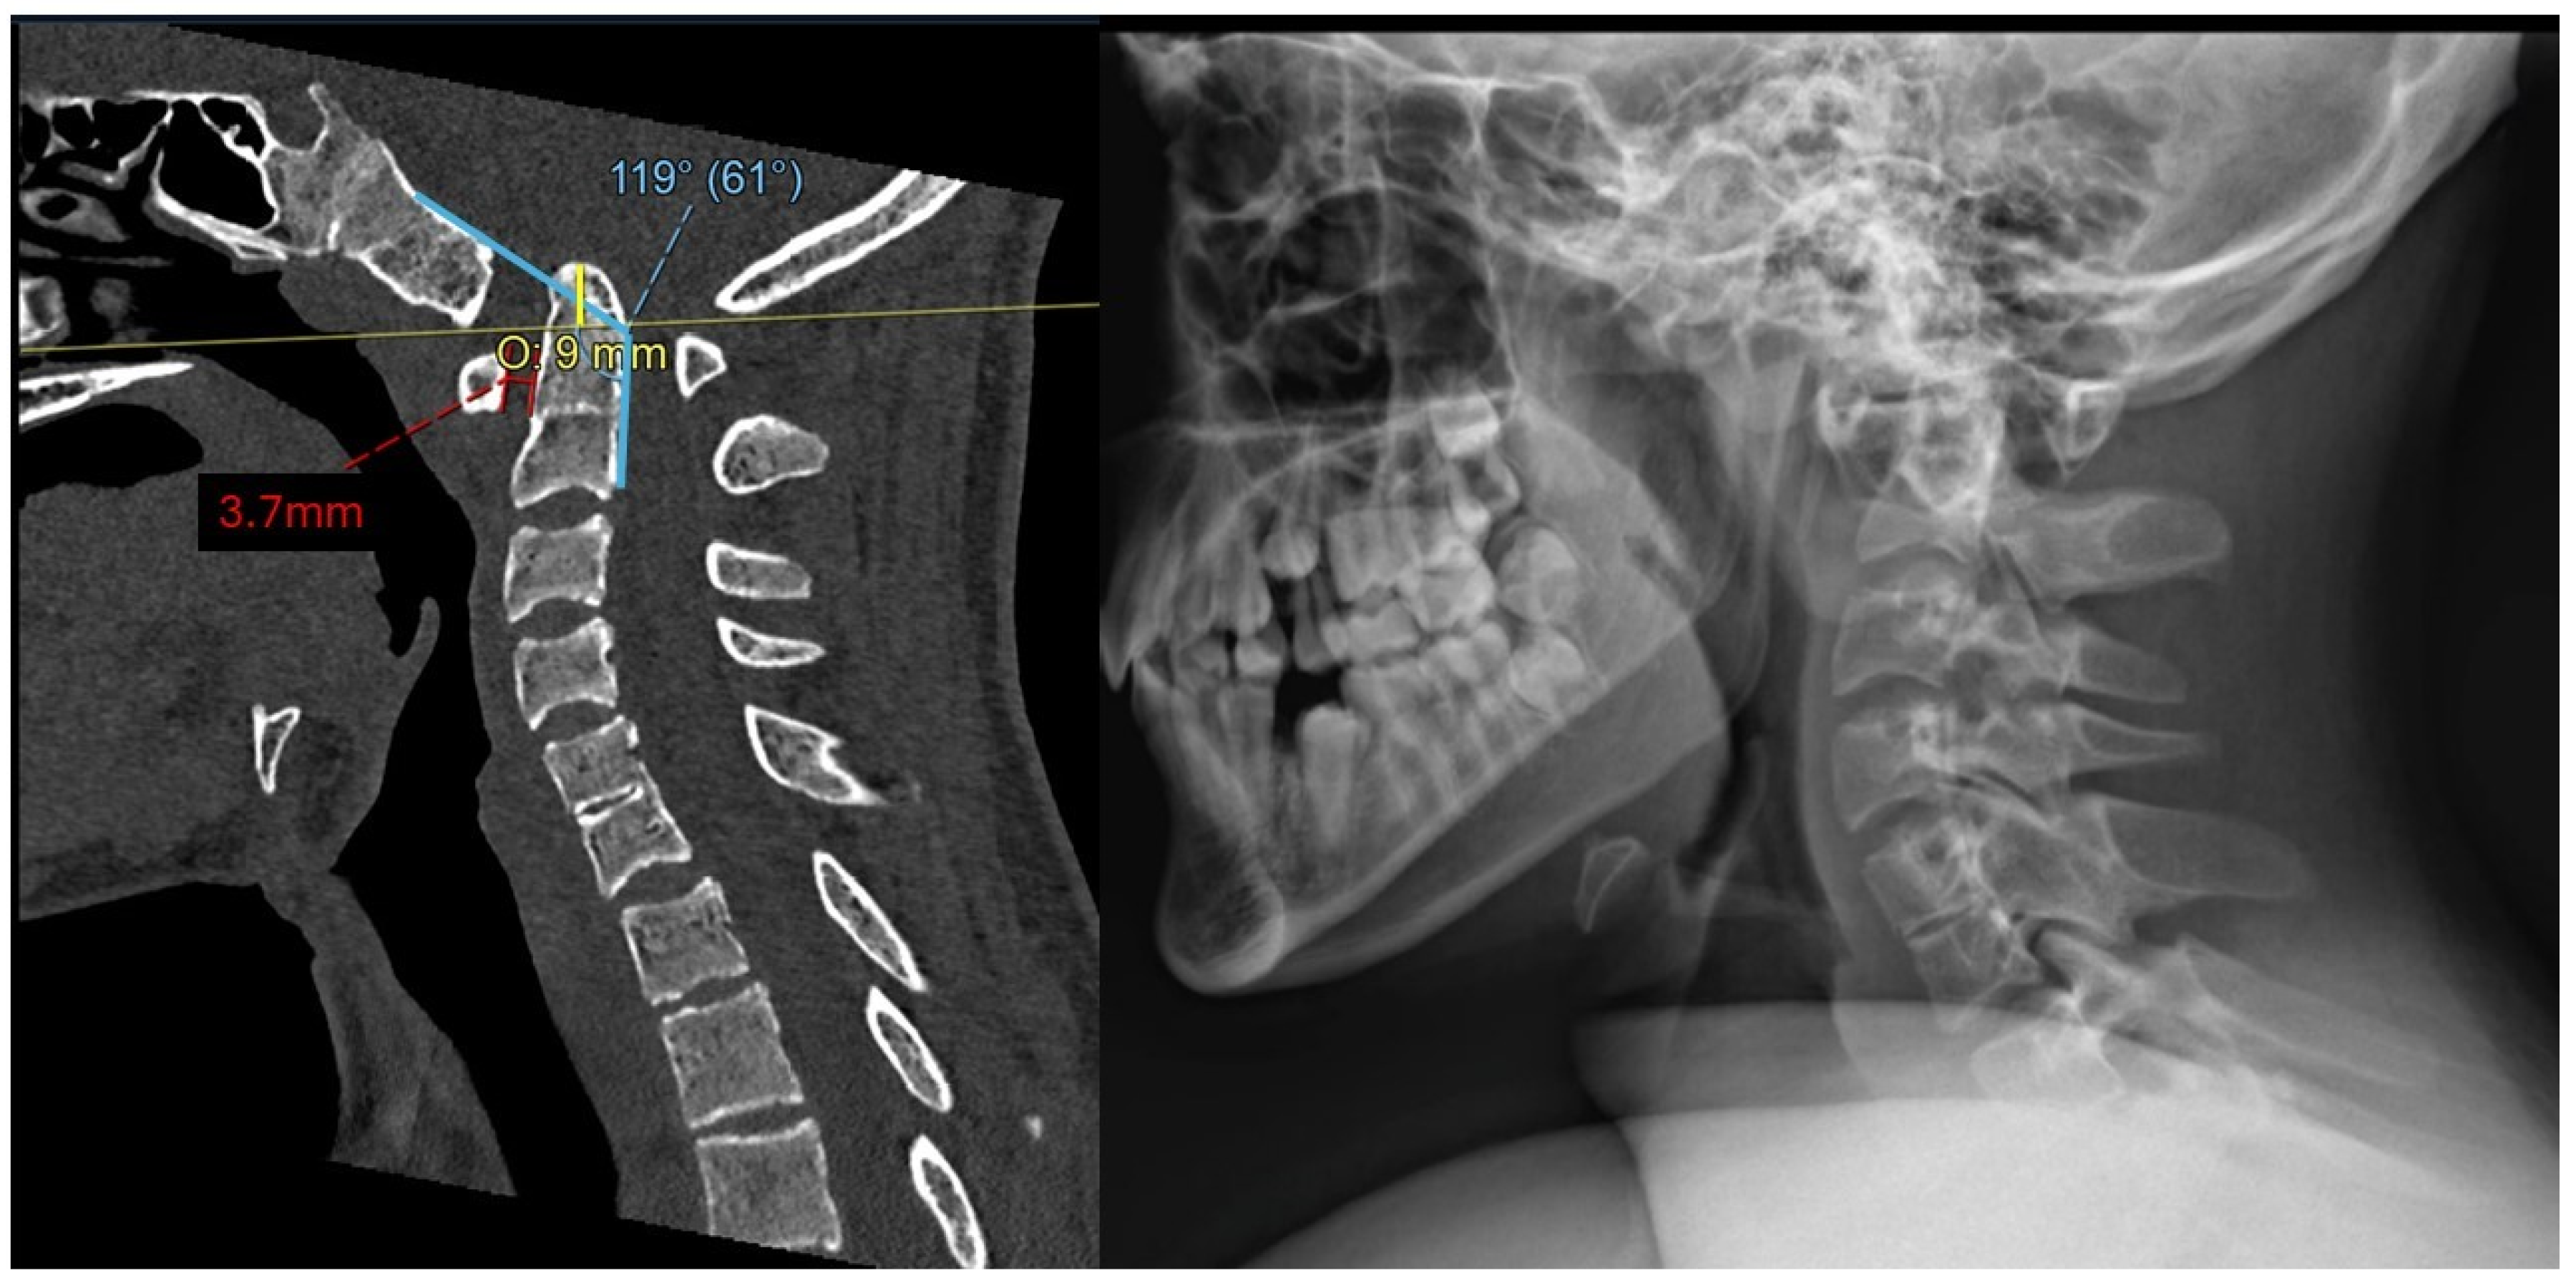

2.2. Imaging and Diagnosis